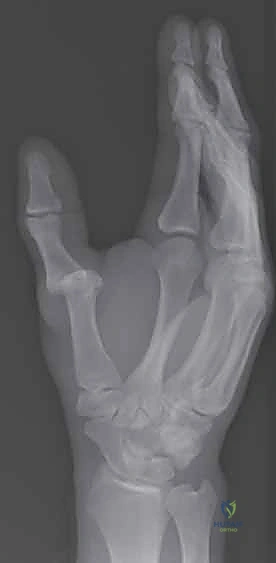

2. التصوير بالأشعة السينية (X-rays)

يُعد التصوير الشعاعي الخطوة الأولى لاستبعاد وجود كسور مصاحبة. في كثير من الأحيان، ينسلخ الرباط ويسحب معه قطعة صغيرة من العظم (Avulsion fracture). كما يتم أخذ صور أشعة تحت الإجهاد (Stress X-rays) لتوثيق عدم الاستقرار.

يحدث الخلع (Dislocation) عندما تخرج الأسطح المفصلية للعظام المكونة للمفصل عن مسارها الطبيعي بشكل كامل بسبب قوة خارجية شديدة. أما الخلع الجزئي (Subluxation) فيعني خروجاً جزئياً مع بقاء بعض التلامس بين العظام.

في المقابل، عدم الاستقرار (Instability) هو حالة قد تكون حادة أو مزمنة، وتنتج عن تمزق أو ارتخاء في الأربطة الداعمة (خاصة الرباط UCL)، مما يجعل المفصل يتحرك بشكل غير طبيعي أو "يرتخي" عند تطبيق ضغط عليه، كما يحدث عند محاولة فتح وعاء زجاجي أو الإمساك بمفتاح.